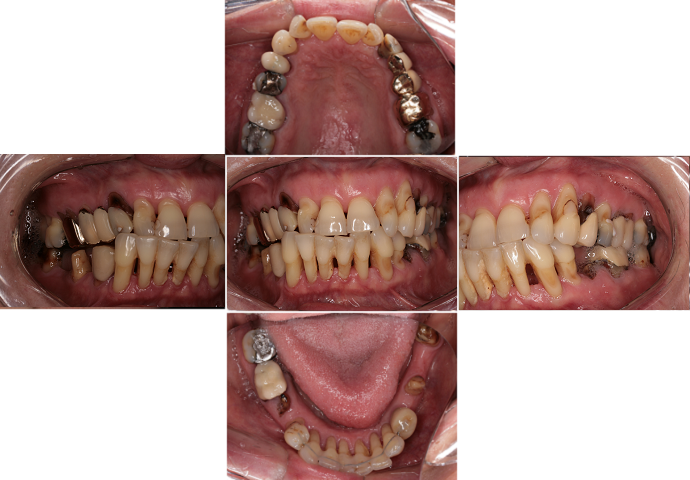

3) fotodokumentace - fotografie stavu chrupu a otisky na studijní modely

Fotodokumentace a model se provádí u pacientů s potřebou kompletní rekonstrukce chrupu.

Foto 9-13: Fotodokumentace situace v ústech - vlevo, vpravo, uprostřed, v horní a dolní čelisti.